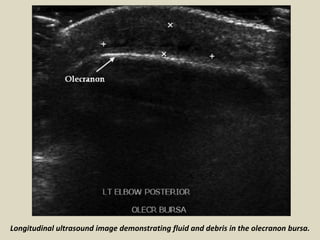

Longitudinal ultrasound image demonstrating fluid and debris in the olecranon bursa.

Longitudinal ultrasound imagedemonstrating fluid and debris in the olecranon bursa.